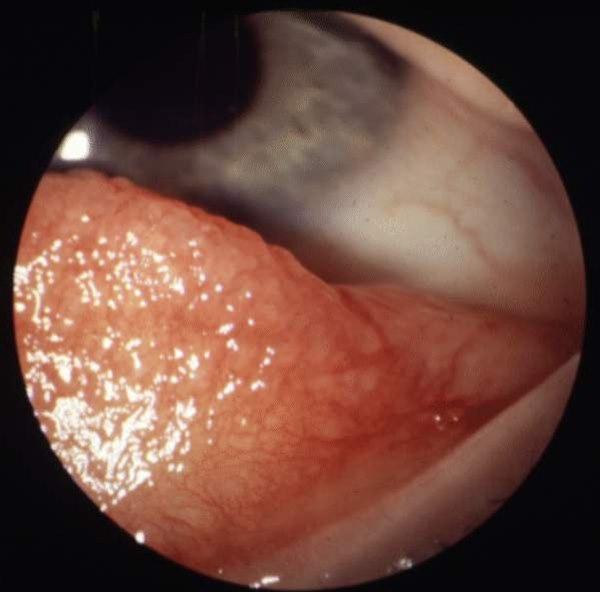

Allergisk øyekatarr, allergisk konjunktivitt, er en tilbakevendende betennelse i øyets ytterste hinne, conjunctiva, på grunn av en allergisk reaksjon. Tilstanden oppstår i forbindelse med episoder der man utsettes (eksponeres) for et allergen (allergifremkallende stoff), og plagene er i de fleste tilfeller sesongavhengige. Tilstanden kan oppstå som akutte anfall eller som perioder med vedvarende plager over dager, noen ganger uker. Det er en godartet men plagsom øyesykdom som ikke er noen trussel mot synet.

Personer med allergisk øyekatarr opplever perioder med røde og rennende øyne samt plagsom kløe i øynene. Tårevæsken er ofte tykkere, mer slimet, enn vanlig. Ofte reagerer de med øyekatarr med ubehag på sterkt sollys eller annen kraftig belysning.

Det er typisk at begge øynene rammes ved en allergisk øyekatarr. Mange pasienter med allergisk øyekatarr har også andre allergiske plager som nevnt over, som høysnue, eksem og astma. De vanligste utløsende faktorer er pollen, dyrehår, kosmetikk og øyedråper, men ofte klarer man ikke å finne en sikker årsak til øyekatarren.

Allergisk konjunktivittDet er vanlig å skille mellom akutt og kronisk allergisk øyekatarr. Akutt øyekatarr er oftest sesongavhengig (pollen), men tilstanden kan også være helårlig når man reagerer på for eksempel husstøvmidd eller dyrehår. Kronisk allergisk øyekatarr er ikke like vanlig, men ofte svært plagsomt. Det er overhyppighet av kronisk allergisk øyekatarr hos personer med eksem.